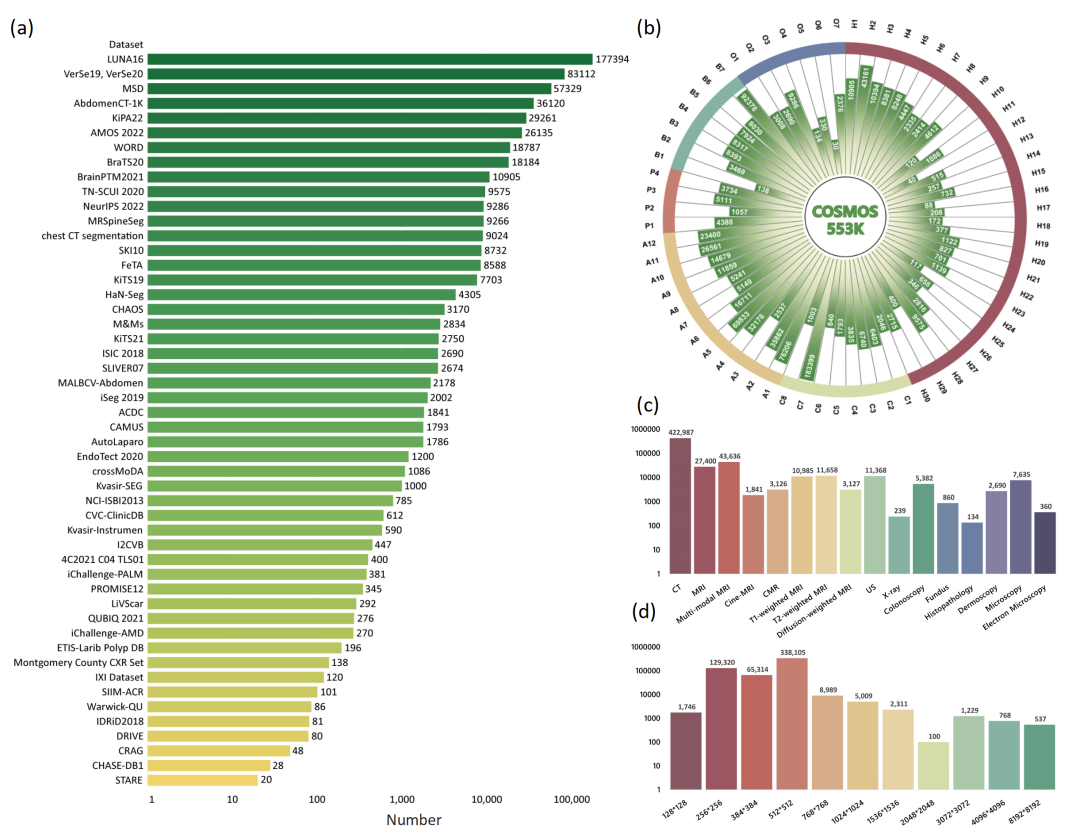

为了全面评估分析SAM在医学影像分割上的表现,团队收集并标准化了52个公共数据集,最终整理构建了一个包含16种影像模态和68种生物医学领域分割目标(表1)的大型医学影像分割数据集COSMOS 553K,数据集的展示见图1,统计信息见图2:

图2 COSMOS 553K的统计信息。(a)收集到的公开数据集处理后的数据量;(b)目标类别的直方图分布;c)影像模态的直方图分布;(d)图像分辨率的直方图分布。